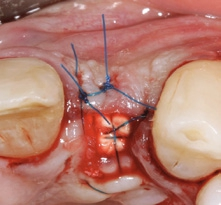

Mit der PEEK-Abdeckkappe, die über einen Klickmechanismus in die Innenkonfiguration des Implantats gesteckt wird, wurde das Implantat verschlossen. Die Abbildung 10 zeigt die optimale prothetisch orientierte Platzierung des Implantats für die Rekonstruktion mit einer direkt verschraubten Hybridabutmentkrone. Von okklusal ist das ausgeprägte bukkale Knochendefizit deutlich zu sehen. Mit einem Gemisch aus autologen Knochenspänen, die während des Bohrvorgangs implantatnah gewonnen worden waren, und Bio-Oss Collagen (Geistlich) wurde der Defekt aufgebaut. Aufgrund ihrer osteogenetischen, -induktiven und -konduktiven Eigenschaften ist der Einsatz von autologen Knochenspänen in der GBR in unserer Praxis Standard. Eine resorbierbare Membran mit verlängerter Barrierefunktion (Memlok BioHorizons) wurde nach Ablösung des Periosts, dem biologischen Konzept folgend, zur Abdeckung des volumengebenden Augmentats in direktem Kontakt zur angrenzenden Knochenoberfläche eingebracht (Abb. 11) [17, 18]. Resorbierbare Kollagenmembranen zeichnen sich dadurch aus, dass der Heilungsprozess der Weichgewebe auch bei Exposition der Membran weiter voranschreitet. Ein Kollagenkegel (Parasorb, Resorba) wurde zum Verschluss des gingivalen Defektbereichs eingesetzt, bevor das Weichgewebe spannungsfrei vernäht (Prolene 5-0, Ethicon) und ein postoperatives Röntgenkontrollbild gemacht wurde (Abb. 12–14). Die temporäre Versorgung erfolgte durch eine Kunststoff-Klebebrücke.